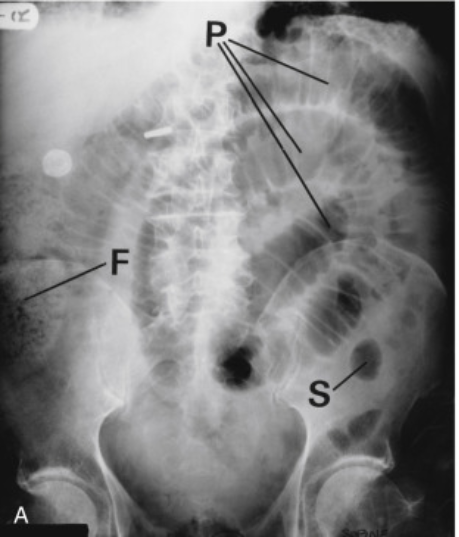

What does this x-ray show?

Mid small bowel obstruction.